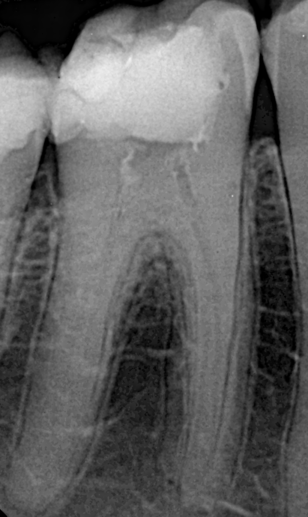

Pre-operative X-ray showed:

- Fully obliterated mesial canals (MB: mesio-buccal; ML: mesio-lingual).

- Obliterated apical third of the distal canals (DB: disto-buccal; DL: disto-lingual).

- Slight abrupt apical curvature in the distal canals.